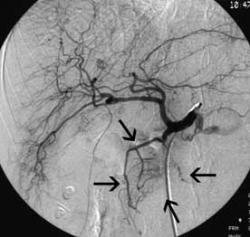

Мне кажется кальцинаты практически в любом органе не является признаком здоровья(коронары,молочные железы, панкреас). Поэтому при их выявлении надо дообследовать пациента и поставить его на диспансерный учет по возможности. Теперь по поводу больших образований головки поджелудочной железы, согласен это скорее признак доброкачественности из-за локализации процессса. Тем не менее, наряду с обязательным контрастированием при КТ, хорошо бы проводить биопсию образования для определения тактики лечения. Для примера привожу следующий случай - пациентка 57 лет при МСКТ выявлена опухоль 6х5 см головки поджелудочной железы(стрелка) с неравномерным накоплением контраста в портальную фазу. Механической желтухи нет. При ангиографии из общей печеночной артерии отмечается наличие объемного образования 6х5 см в головке поджелудочной железы(стрелки). Далее катетер проведен в гастродуоденальную артерию (гда), при суперселективном контарстировании опухоль кровоснабжается из системы верхних панкреато-дуоденальных артерий(впда), имеется типичная опухолевая экстравазация в паренхиму железы с симптомом "озер" и "лужиц" (звездочки). При КТ это выглядит как неоднородность контрастирования. Ангиография была элементом рентгенохирургического вмешательства, больной проведена суперселектвиная эмболизация опухоли железы смесью липиодола(жировой контраст как носитель) и гемзара(противоопухолевый препарат 1 ряда для лечения рака поджелудочной железы). Если интересно выложу картинки этапа эмболизации и контрольной артериографии.